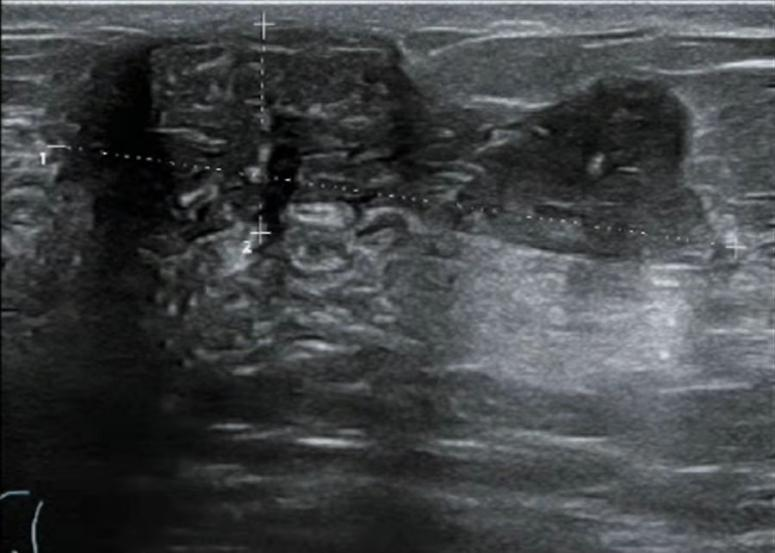

2021.7.6 钼靶示:右乳外上象限肿块,考虑乳腺癌(BI-RADS-5类)右腋下肿大淋巴结,M灶可能。

右乳外上象限不规则高密度肿块,边缘毛糙,大小约3.3×2.7cm,邻近皮肤牵拉增厚,右腋下见肿大淋巴结。

图2. 钼靶

(3 cycle 后)2021.9.21 钼靶示:右乳外上象限不规则形肿块明显缩小,右腋窝淋巴结亦较前缩小。

图6. 钼靶